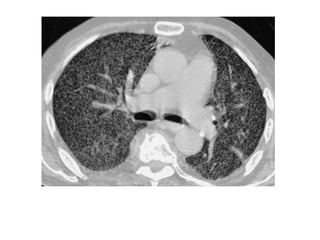

• #51 Paciente masculino de 63 años que refiere tos, disnea y dolor torácico derecho de aproximadamente siete días de evolución. El examen físico revela hipo ventilación en hemitorax derecho. Como dato positivo de laboratorio presenta VSG aumentada. Se solicita inicialmente una radiografía de tórax frente en la cual se observa, radioopacidad basal derecha con broncograma aéreo que borra el seno costofrénico homolateral. Engrosamiento pleural difuso que impresiona comprometer pleura mediastínica. Dados los hallazgos en la radiografía se decide ampliar el diagnostico solicitándole una TAC de tórax con contraste endovenoso en la cual se observa engrosamiento circunferencial pleural de hemitorax derecho. Atelectasia de segmentos inferiores con broncograma aéreo. Pequeña área líquida tabicada. Adenomegalias mediastinales en región prevascular, pretraqueal retrocavo y ventana aortopulmonar. Caja torácica sin alteraciones tomográficamente demostrables. Estructura y densitometría osteoarticular de l raquis dorsal normal. DIAGNOSTICOS DIFERENCIALES: • Engrosamiento pleural: Derrame organizado, hemotórax, piotorax, cirugía previa, radioterapia, exposición al Asbesto. • Tumores Benignos: lipomas, tumores fibrosos, esplenosis torácica. • Tumores malignos: MTTS de pulmón, mama, linfoma. • Mesotelioma maligno. DIAGNOSTICO DEFINITIVO: • MESOTELIOMA MALIGO